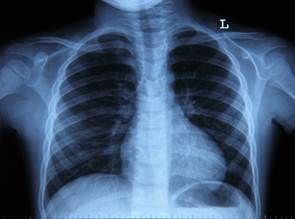

Флюорография (малоформатная рентгенография) – рентгенография с уменьшенным размером изображения, получаемого на флюоресцирующем экране (лат. fluor – течениие, поток); её применяют при профилактических исследованиях органов дыхания (рис 4).

Рис. 4. Флюорография грудной клетки

Цель исследования: ранняя диагностика заболеваний бронхо-легочной системы.